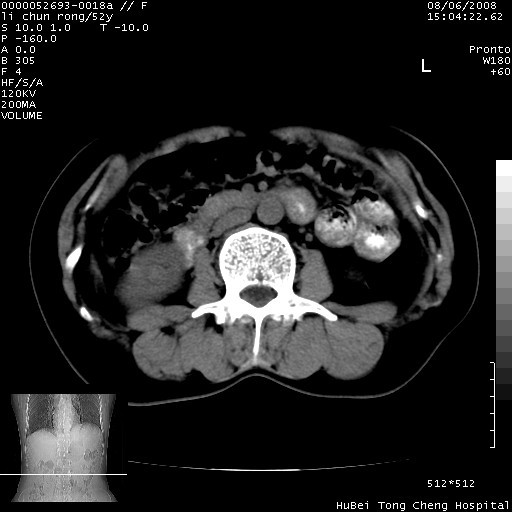

以下是引用云翔在2008-8-7 6:20:00的发言:[br]胰尾部囊性病变,考虑假囊肿,结合实验室检查疾病史

以下是引用zjzjr在2008-8-7 8:38:00的发言:[br]支持胰腺炎伴假囊肿形成,左肾小囊肿.少量腹水.

以下是引用随光逐影在2008-8-7 9:12:00的发言:[br]1)考虑胰腺炎伴假性囊肿形成可能性大;胰腺囊腺瘤待排。2)左肾小囊肿。3)少量腹水。